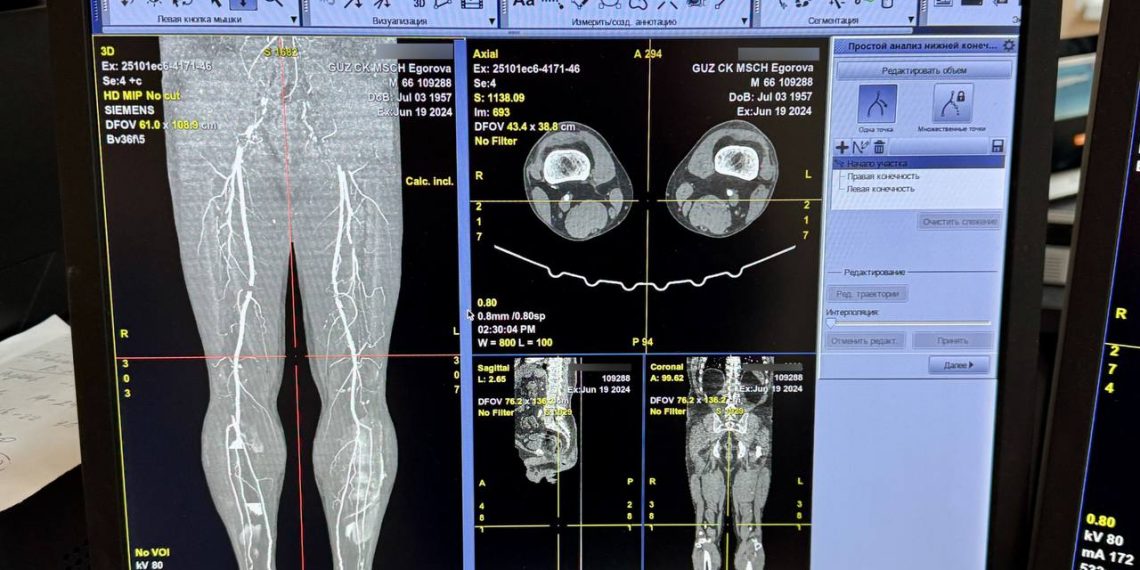

Мужчина находился на лечении в эндокринологическом отделении с множественными осложнениями, включая стеноз и окклюзию артерий нижних конечностей до 75 процентов. У него была выявлена критическая ишемия нижней конечности, требующая хирургического вмешательства. КТ-ангиография подтвердила окклюзию левой бедренной артерии, и было рекомендовано эндоваскулярное вмешательство.

Больного госпитализировали в хирургическое отделение ЦКМСЧ, где провели баллонную ангиопластику со стентированием поверхностной бедренной артерии. Благодаря своевременной диагностике и успешной операции удалось сохранить ногу.